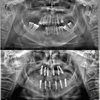

علاج الزرعات السنية